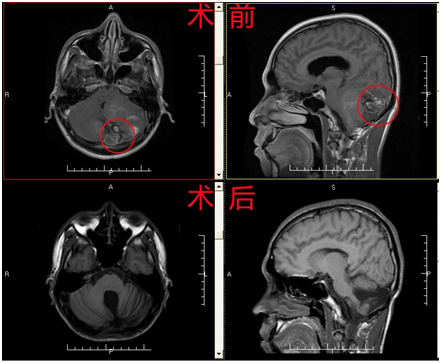

病例2 小脑动静脉畸形

患者陈某,男,22岁,因“反复头痛10年余,复发加重2月”入院;查体:未发现明显阳性体征;辅助检查:我院MR检查回示:左侧小脑半球血管性疾病可能,伴小脑扁桃体下疝;入院诊断:1、左侧小脑半球及蚓部血管畸形并破裂出血? 2、小脑扁桃体下疝;予行“小脑蚓部及左侧小脑半球AVM切除术+血肿清除术”,术程顺利,术后患者恢复良好。